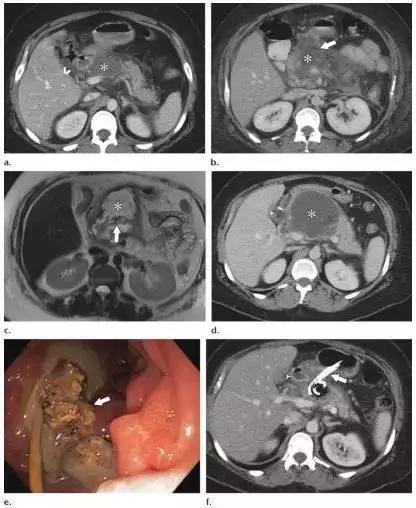

同时受累的亚型:表现为胰腺及胰周无强化坏死物,多累及小网膜囊和肾前间隙(图 3a)。

胰周型:表现为胰腺强化正常,而胰周坏死,坏死物可包括不等量的液体和和非液性成分,约占坏死性胰腺炎的 20%(图 3b)。

图 3 坏死性胰腺炎亚型在增强轴位 CT 的表现。a 胰腺和胰周同时受累的 58 岁女性患者,胰体无强化(*),正常强化的胰尾(黑箭头),小网膜囊内 ANC(白箭头)。b 仅胰周受累的 18 岁男性患者,可见一周为大片不均质密度(箭头),和 ANC 相符。胰腺实质密度正常(*)。c 仅胰腺实质受累的 33 岁男性患者,可见大片局限无强化的胰腺实质和脂肪密度(*),诊断为 WON。仅周边可见少量残余强化的胰腺实质(箭头)